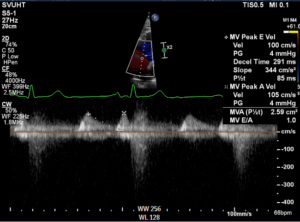

Waveform from CW Doppler interrogation of mitral valve inflow is shown below. Findings are consistent with which of the following